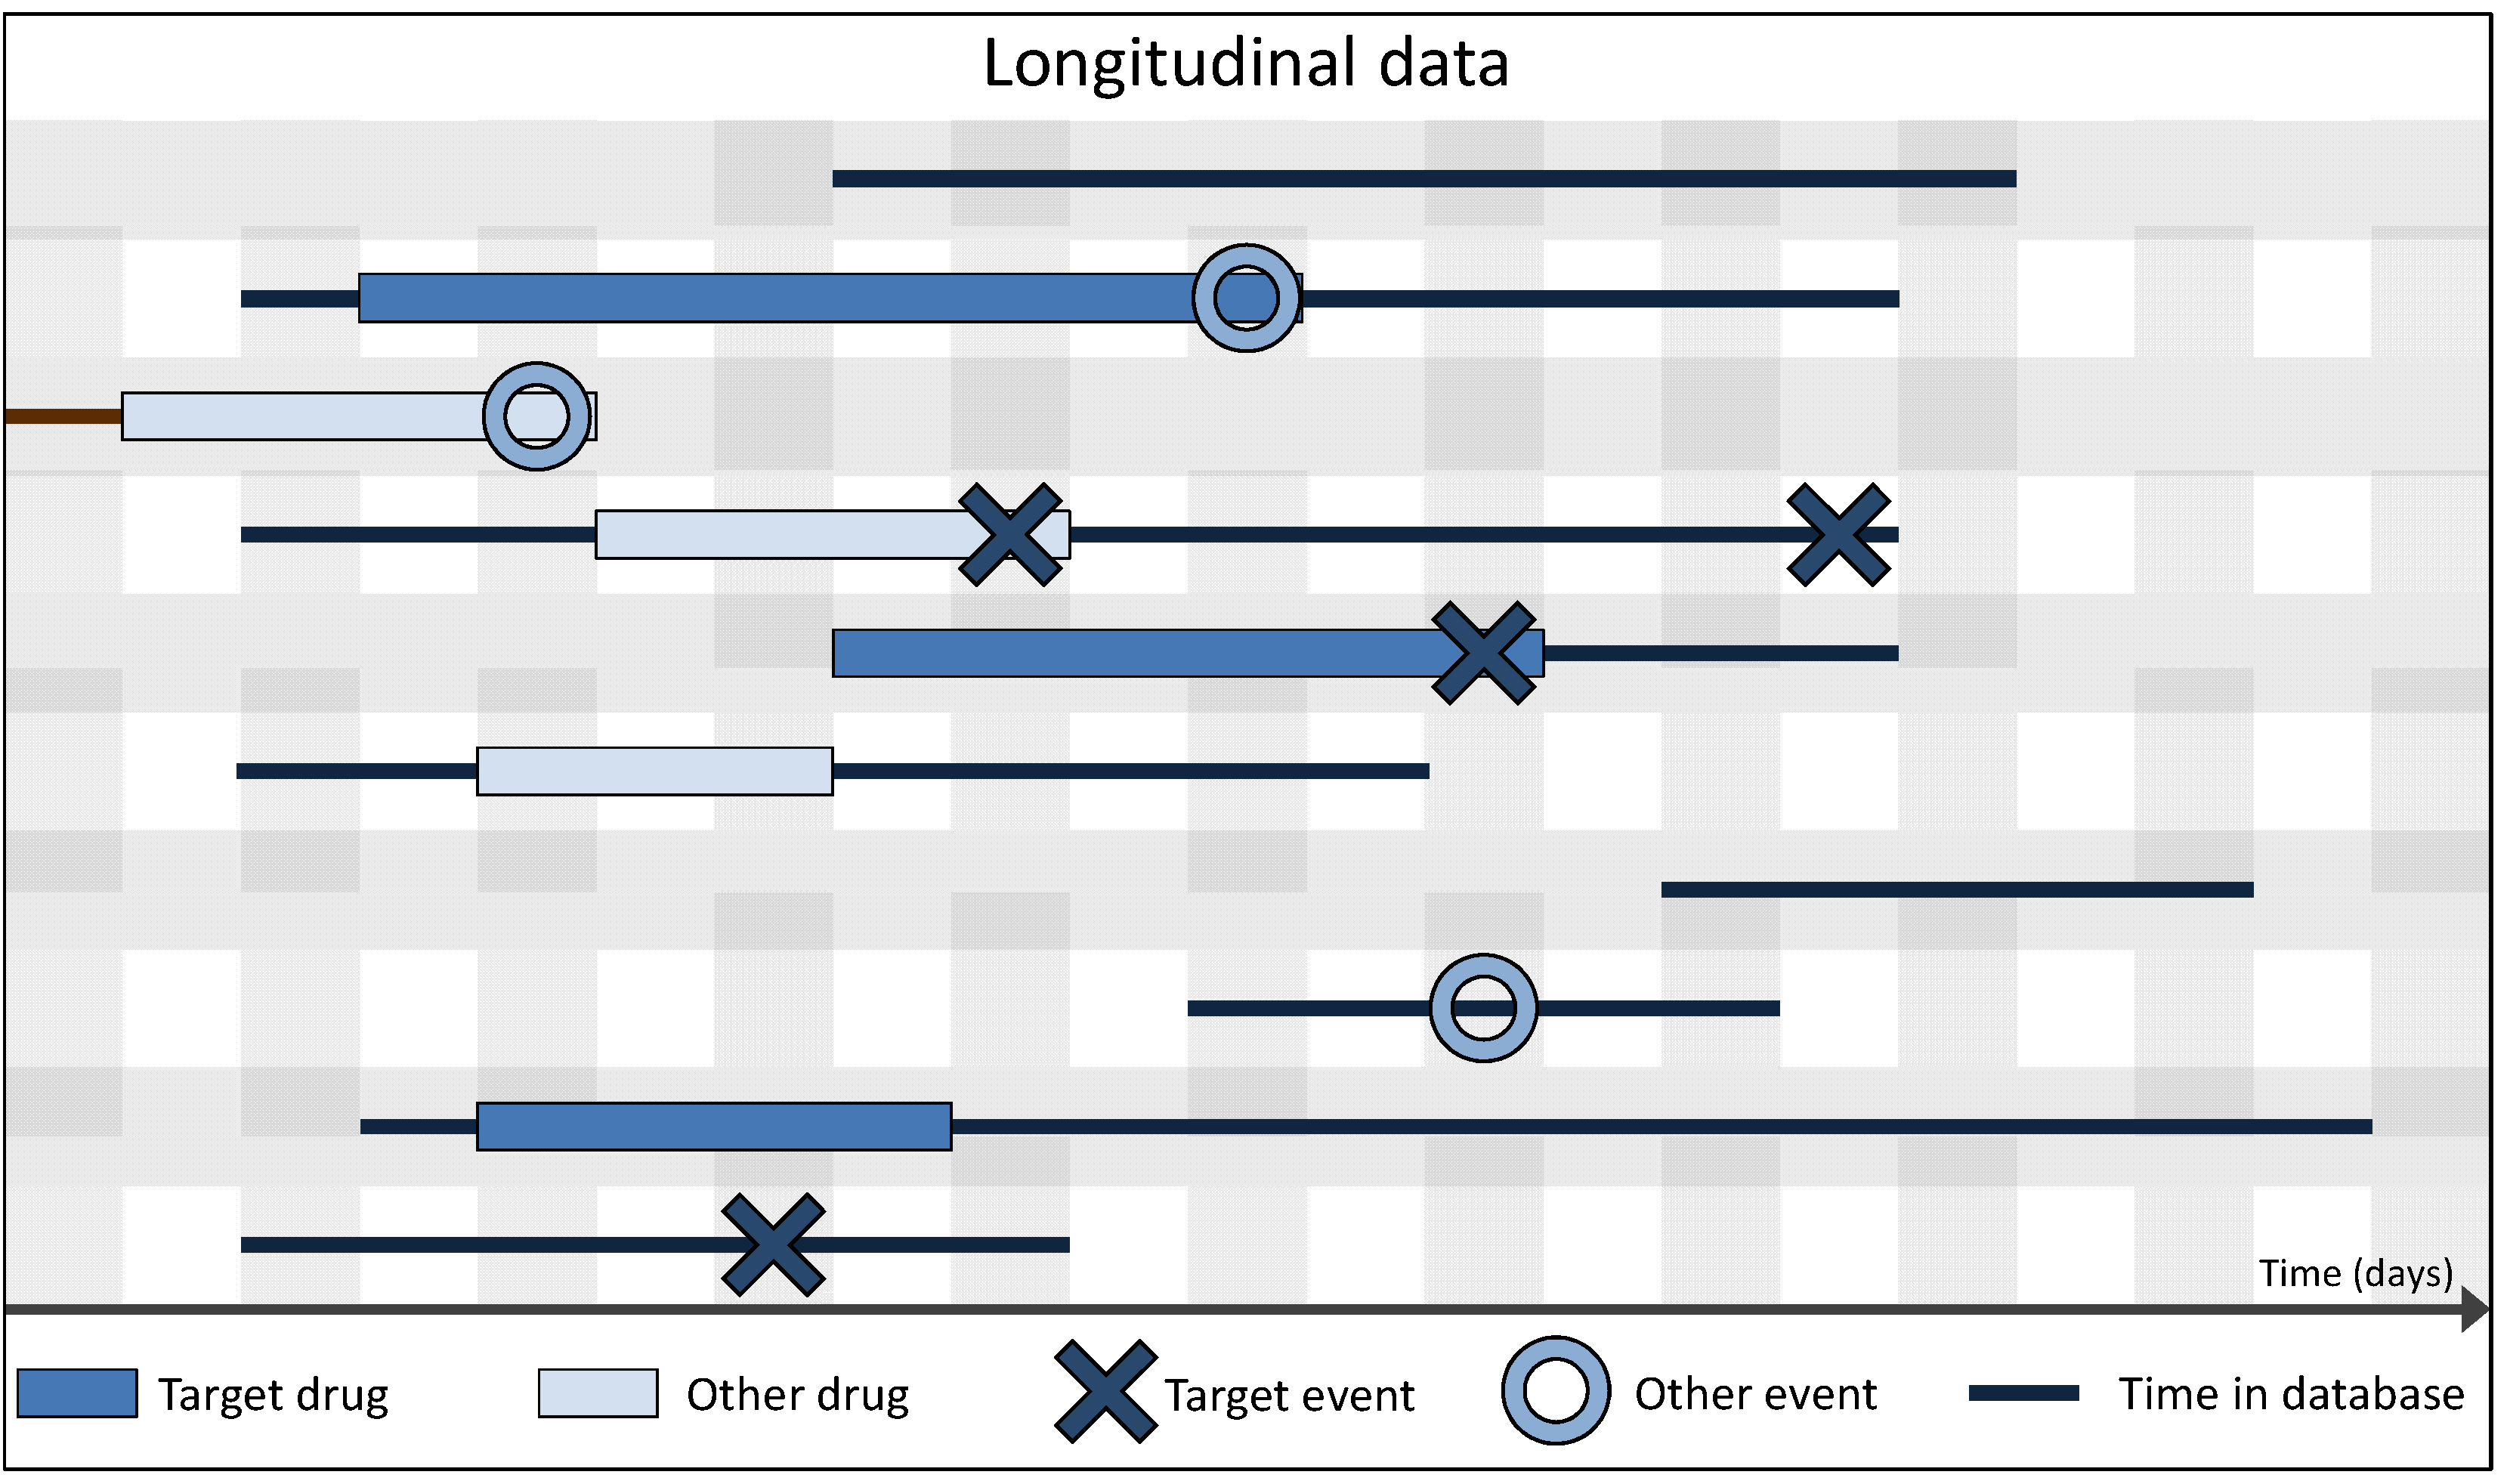

3.2. Spontaneous vs. Longitudinal Data

3.4. Definition of Exposure and Event in Longitudinal Data